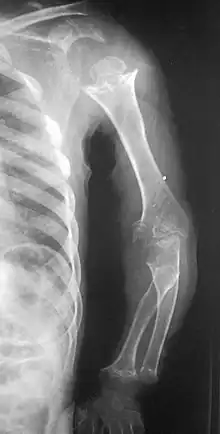

Pseudoachondroplasia. Shoulders and Humeri. Note the dysplastic proximal humeral epiphyses, metaphyseal broadening, irregularity and metaphyseal line of ossification. These changes are collectively known as "rachitic-like changes". Lesions are bilateral and symmetrical.

Disproportionate short stature, deformity of the lower limbs, short fingers, and ligamentous laxity give pseudoachondroplasia its distinctive features. The average height of adult males with the condition is around 120 centimeters (3 ft, 11 in), while adult females are typically around 116 cm (3 ft, 9in). Affected individuals are not noticeably short at birth. Patients with pseudoachondroplasia present with gait abnormalities, lower limb deformity, or a retarded growth rate that characteristically appear at age 2–3 years. Disproportionate short stature is characterized by shortening of proximal limb segments (humeri and femora) also called rhizomelic shortening. Other known clinical features include, genu valgum/varum, brachydactyly (short fingers), supple flexion deformity of the hips, knees, hyperlordosis of lumbar spine, rocker bottom feet and broadening of the metaphyseal ends of long bones especially around the wrists, knees and ankles. Patients with pseudoachondroplasia have normal intelligence and craniofacial features.[2][4][5]

• Together with rhizomelic limb shortening, the presence of epiphyseal-metaphyseal changes of the long bones is a distinctive radiologic feature of pseudoachondroplasia.

• Dysplastic/hypoplastic epiphyses especially of shoulders and around the knees.

• Metaphyseal broadening, irregularity and metaphyseal line of ossification. These abnormalities that are typically encountered in proximal humerus and around the knees are collectively known as “rachitic-like changes”.

• Radiographic lesions of the appendicular skeleton are typically bilateral and symmetric.